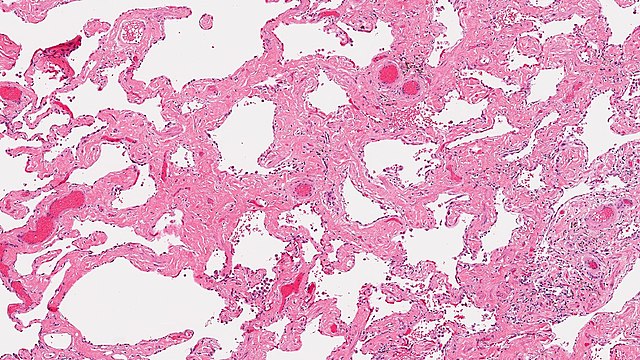

La BR-PID, pour sa part, correspond à un tableau clinique associant toux chronique et dyspnée d’effort, associées ou non à perturbations modérées des explorations fonctionnelles respiratoires. Il est impossible de différencier histologiquement BR et BR-PID, la clinique permettant de trancher entre l’une et l’autre. La PIDE, pour sa part, correspond à une accumulation intra-alvéolaire de macrophages pigmentés qui finit par prédominer, tout en s’associant à une hyperplasie des pneumocytes de type II. Sa traduction radiologique consiste en l’apparition de plages de verre dépoli extensives, le plus souvent bilatérales et symétriques, qui prédominent toutefois au niveau des lobes inférieurs et en périphérie des champs pulmonaires.